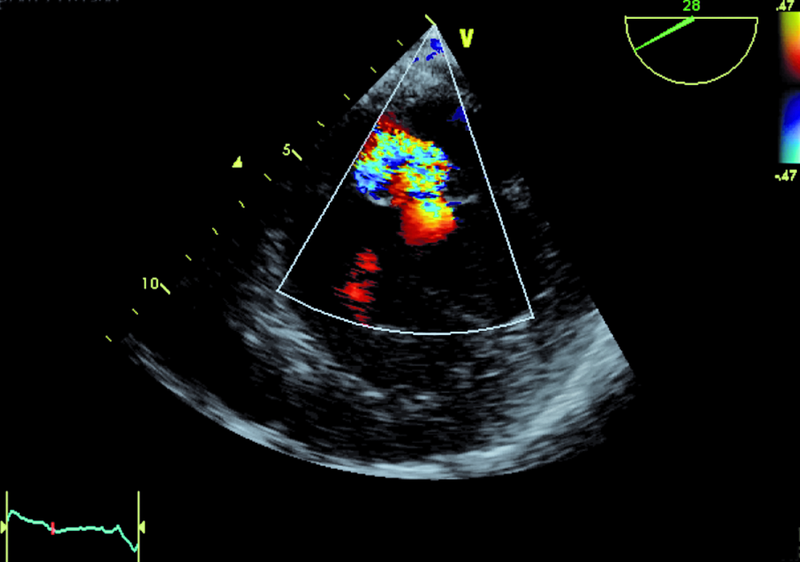

Mężczyzna, lat 68. Jakie patologie można rozpoznać na rycinach?

2. Duża niedomykalność zastawki mitralnej (ryc. 2, 5).